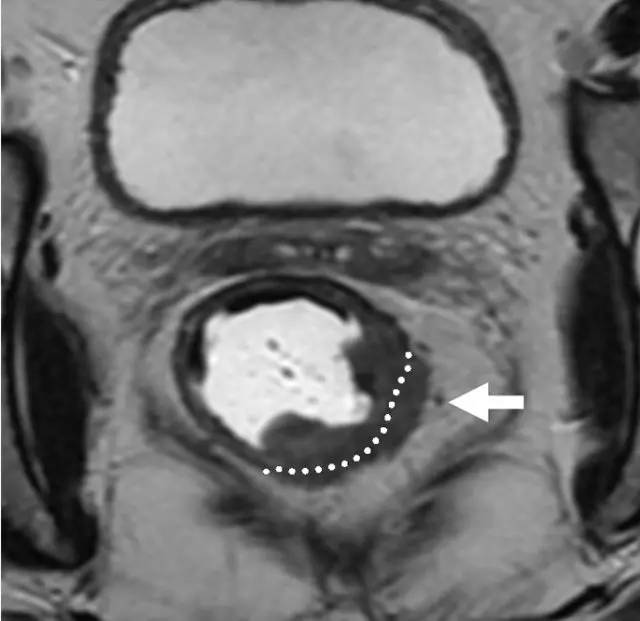

MR 无法区分肿瘤是局限于黏膜下层还是浸润至固有肌层,直肠内超声(US)能够更准确地区分 T1 和 T2。T1~2 期肿瘤未穿透肠壁,预后较好,T1~2 期 MRI 上可见直肠肠壁完整的黑色边界。

图 5 远端直肠半圆形 T2 肿瘤,与外部肌层分界明显